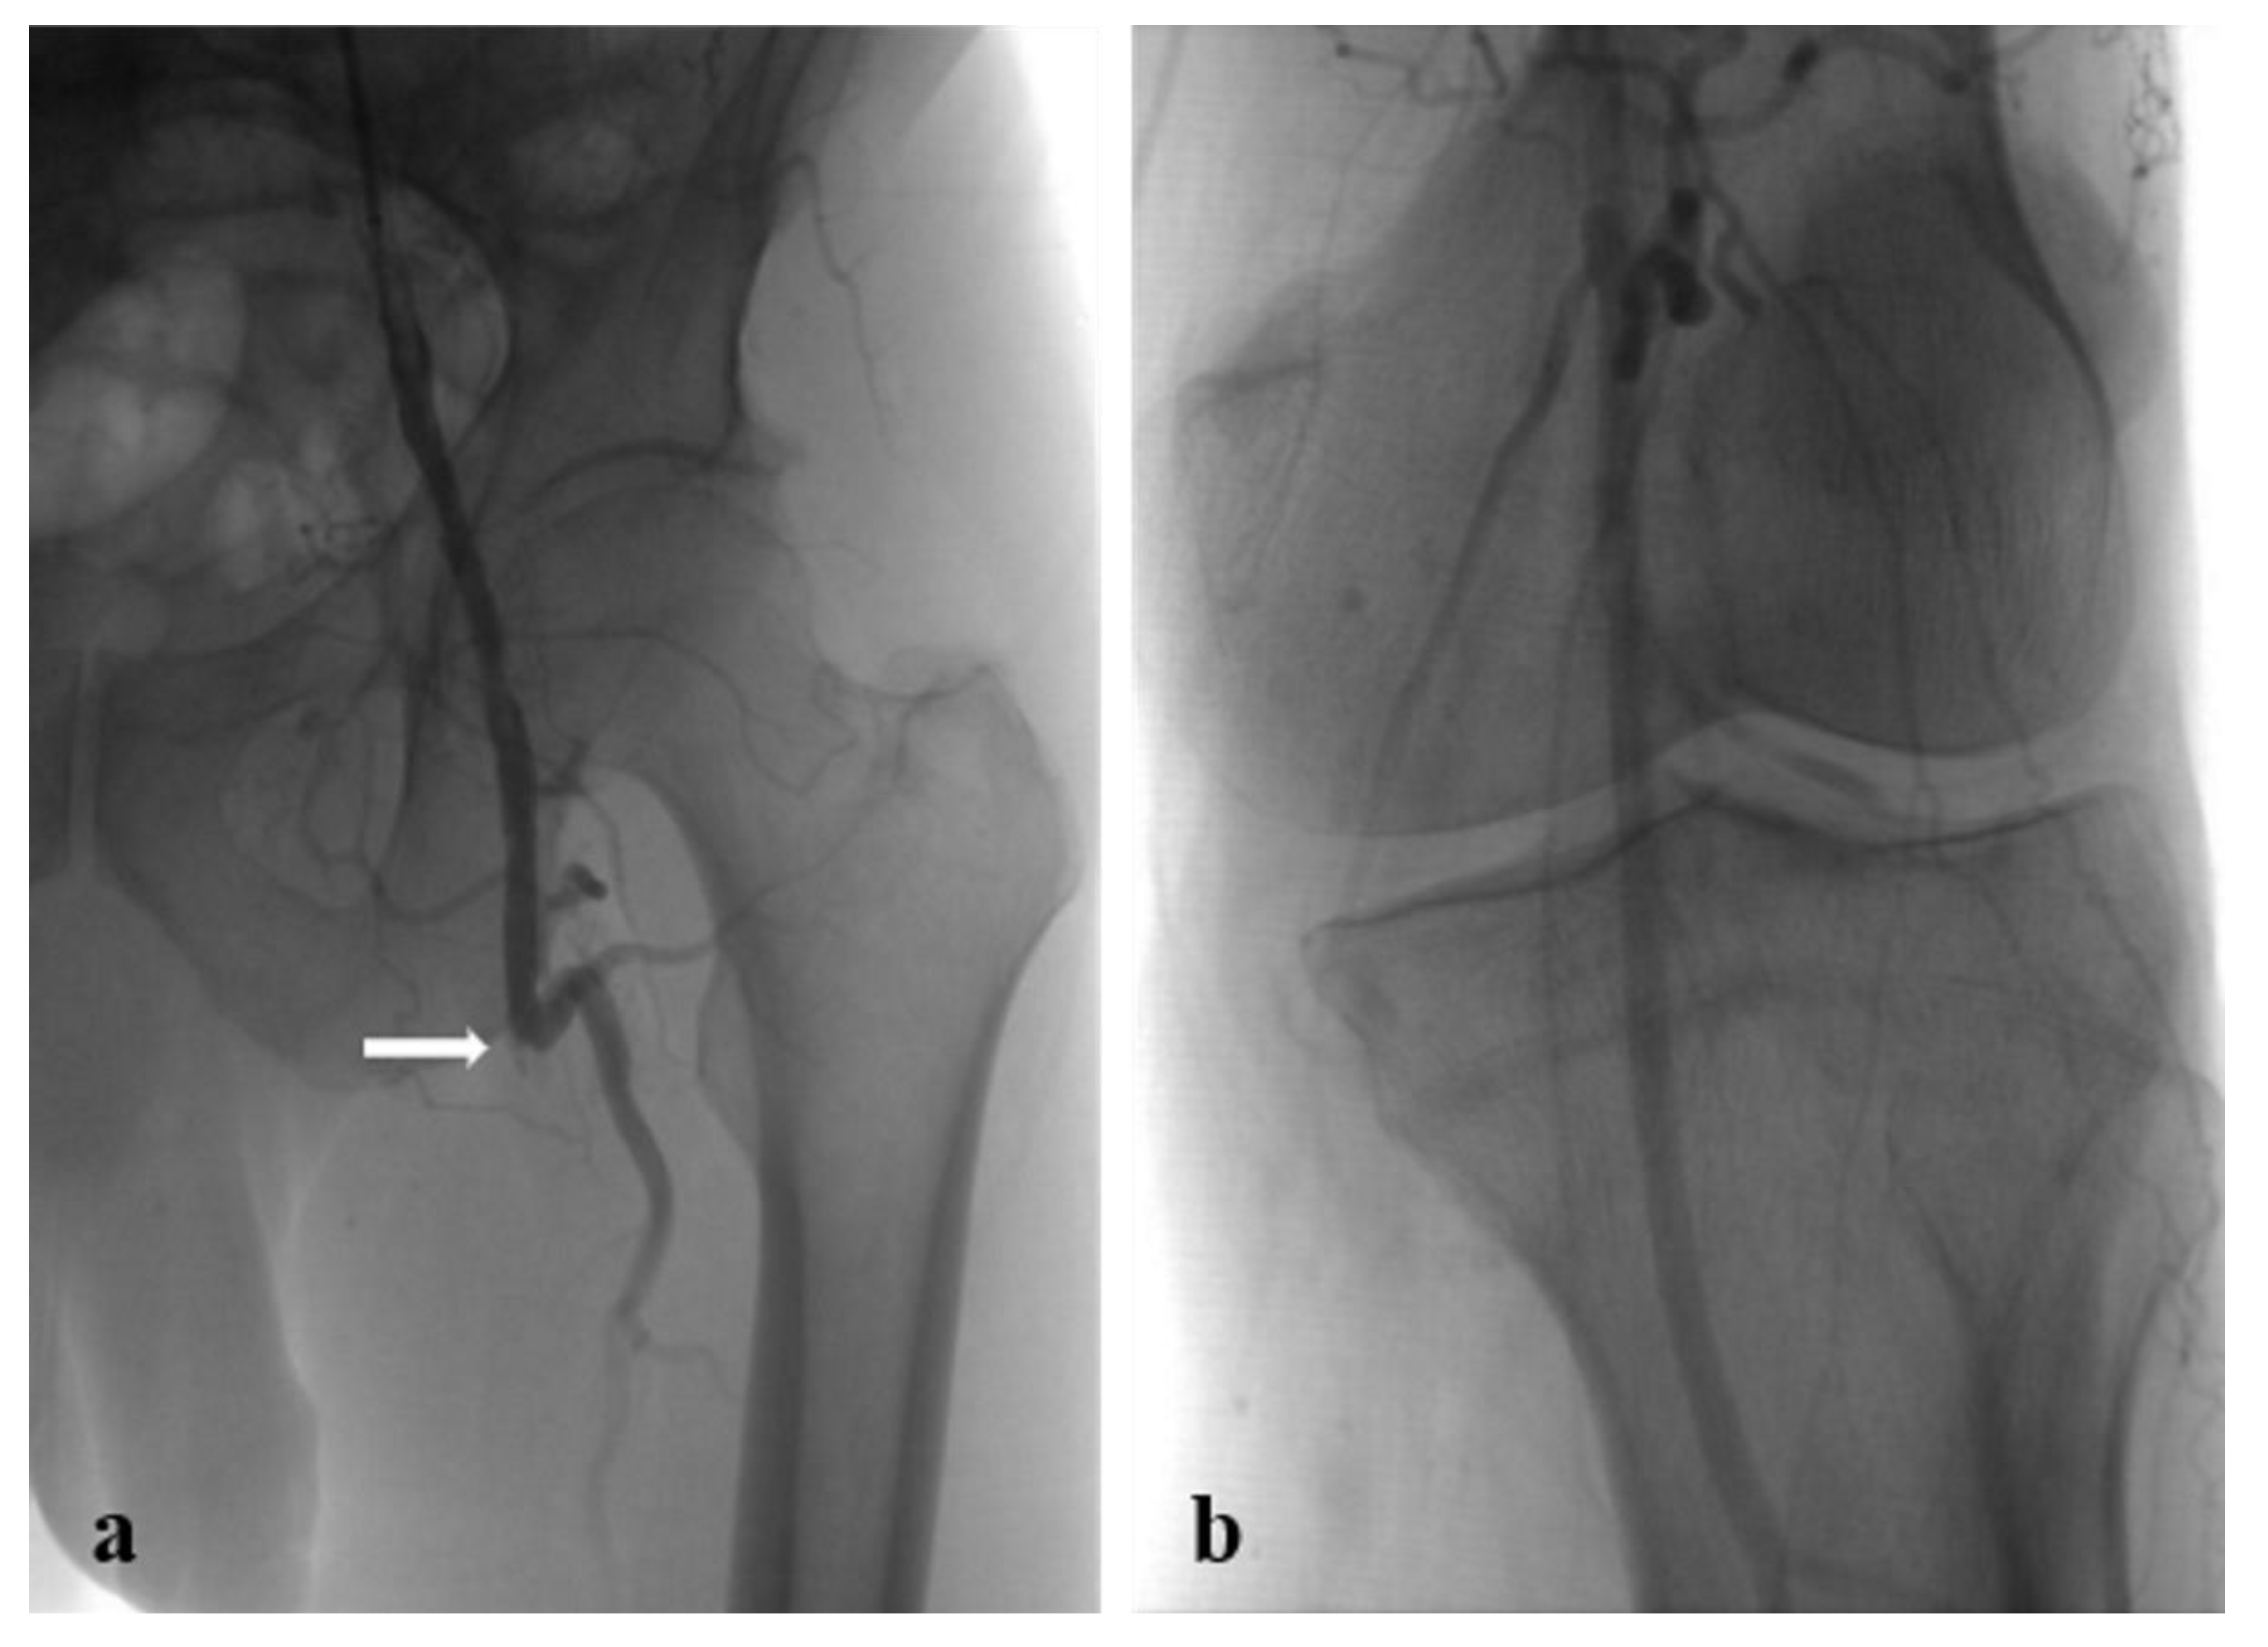

Figure 3. Preoperative angiograms: (a) occluded prosthetic FB bypass (white arrow: proximal anastomosis); (b) popliteal artery revascularized by collateral vessels.

It was decided to proceed with a US-guided approach via the right common femoral artery with 6 Fr introducer sheath after local anaesthesia (Lidocaine Hydrochloride 2%) and systemic heparinization (5000 UI). A preliminary angiogram through the introducer sheath confirmed CT findings and highlighted the widespread atheroma of the common iliac-femoral axis and medium-grade stenosis in the external iliac artery. The right-left crossover was performed with a 6 Fr 45 cm introducer sheath conveyed into the left common iliac artery. A left lower extremity arteriogram confirmed the occlusion of the FP bypass with blood supply rehabilitated in the popliteal artery (Figure 3a,b). The peroneal artery was patent and the tibial arteries were not opacified.